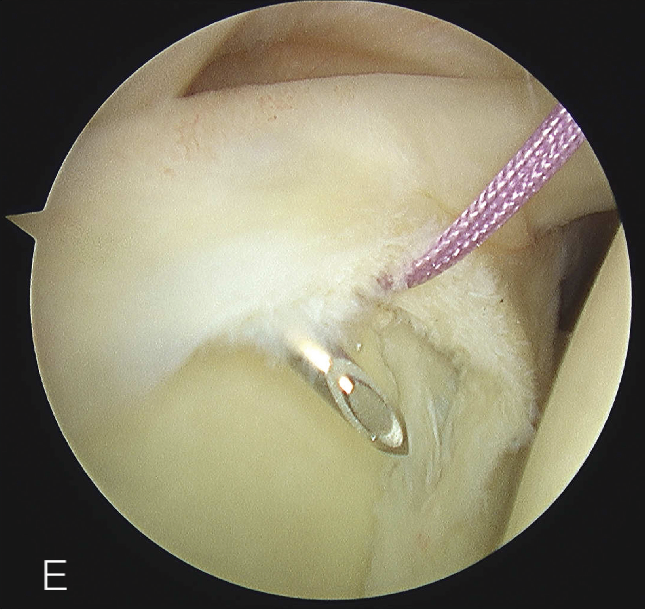

B. 应首先用腰椎穿刺针确定辅助入路的恰当位置和方向。然后在皮肤上做一个小切 A B 口,钻头导向器置入关节。

修复处准备